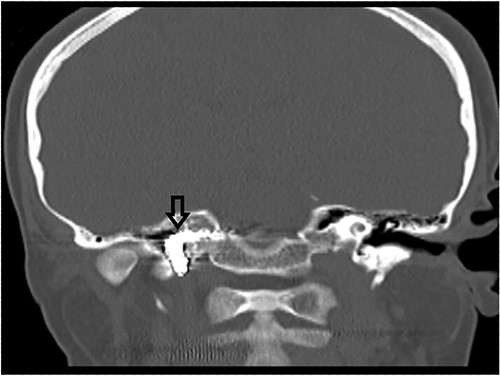

Computed tomography (CT) scan showed complete bilateral heterogenic opacification of paranasal sinuses, suggestive of chronic AFRS (Fig. 1). More importantly, there was some dehiscence of the lateral wall of the right sphenoid sinus near the petrous segment of the right ICA (Fig. 1). Having no previous history of head injury, trauma or surgical interventions, the existence for any aneurysmal carotid artery was not thought of.

CT scan, left imaging is an axial view, without contrast, showing complete opacification of all paranasal sinuses with heterogeneous density inside the sinuses; with erosion in the distal part of the right petrous carotid canal abutting the right sphenoid sinus (arrow); right image is a coronal view, showing extensive polyposis with bony erosion in the bony boundaries of the sphenoid sinuses.